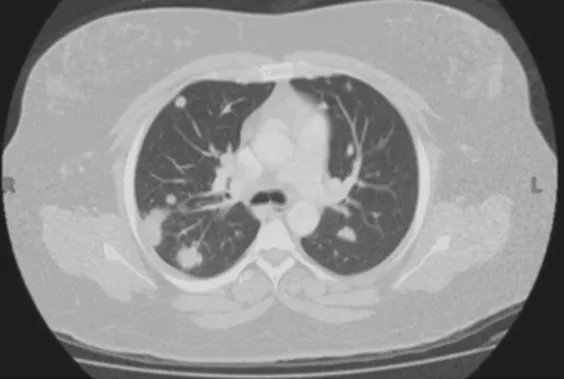

按照肺结节的密度,可分为实性结节、部分实性结节、亚实性或混合性结节、无实性或磨玻璃结节;根据肺结节的数目,可以分为孤立性肺结节(SPN)和多发性肺结节(MPN)。最近多发性肺结节的病人有所增加,临床上针对这类患者的诊断和处理方面还存在许多困难。

在临床上经常手术切除后发现是AAH,关于AAH的病人是否需要手术还存在很大的争议,有的认为不需要手术,观察就可以。那么我们在术前怎么评判是否为AAH?其实具有一定特征。一般来说,多位于肺外周,多<5mm,圆形或类圆形,边界清楚,多发更常见,绝大部分是均匀的纯磨玻璃影,里边没有实性成分。组织学检查AAH呈轻度到中度非典型立方柱状上皮细胞沿肺泡和呼吸性细支气管上皮增殖,无浸润,这样在临床上诊断AAH应该没有问题。但是,如下图所示,这个病人是多灶性病变,现在多灶性结节有所增多,会给临床的处理上带来一定压力。